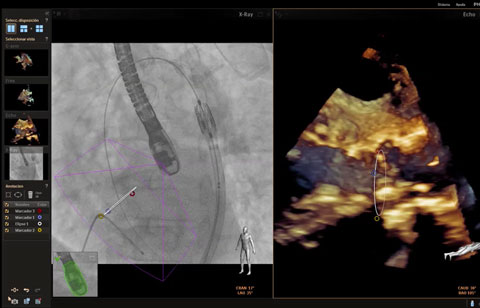

تم تشخيص أحد المرضى لديك بتضيّق في الصمام الأورطي المصحوب بأعراض. يبلغ عمر المريضة 85 عامًا وهي تعاني من السكري وارتفاع ضغط الدم. أنت تدرك خطورة وضعها الصحي ما يجعلها غير مناسبة لجراحة القلب ولكن يسمح لها بأن تكون مرشحة لاستبدال الصمام الأورطي باستخدام القسطرة (TAVR). في يومنا هذا، تمنح حلول التصوير المبتكرة والأجهزة التي تعمل عن طريق الجلد الأمل لبعض المرضى الذين لا تتوفر لهم حتى الآن أي خيارات علاجية أخرى.